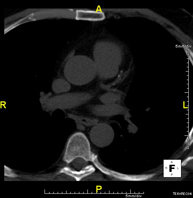

- Thoracic aorta CT angiography

Diagnostic test to examine the thoracic aorta (main artery of the thorax) using CT (Computed Tomography) equipment. This technique requires the use of an iodinated contrast agent, and provides high definition anatomical images. The use of MDCT (Multidetector Computed Tomography) shortens scanning time, reduces radiation dose and improves image quality. The multiple detectors used in certain studies enable imaging to be synchronised with the heartbeat, a technique used to study the aortic valve and aortic root (the first few centimetres), where the heartbeat often distorts images due to movement.